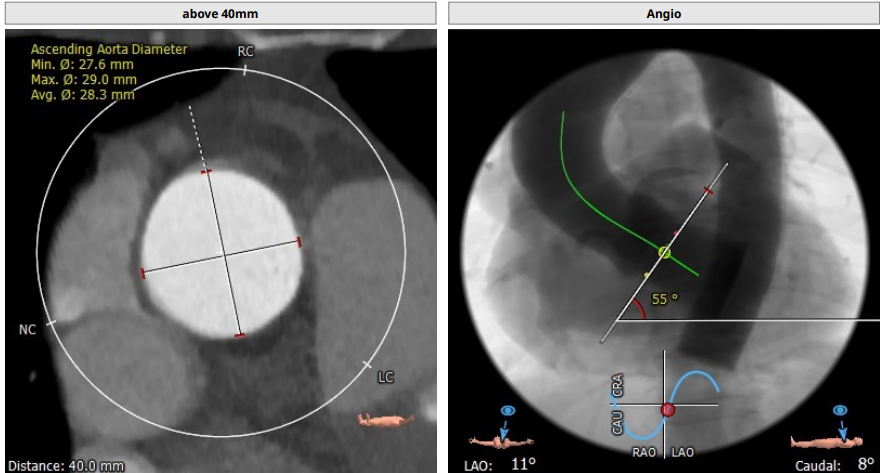

升主动脉(未见)明显扩张,心脏角度:55°

升主:27.6mm*29mm;主动脉成角:55°

患者主动脉瓣呈三叶瓣,轻度钙化,法式窦结构不大,双冠高度可,升主动脉未见明显增宽,心脏角度约55°,左室小,心肌肥厚,主动脉弓部走行较平缓,但有明显钙化斑块,考虑到术中斑块脱落导致的卒中的风险,选择颈内动脉先行植入Emboshield Nav6抗栓塞远端保护装置进行保护,再行TAVR术。

选用18mm球囊进行预扩张,通过造影观察,主动脉瓣重度狭窄,预期病人耐受球囊扩张后的反流。考虑瓣环20.2mm的直径、左室流出道19.9mm的直径、钙化分布等因素,因此判断瓣环结构对瓣膜位置要求极高,有较高风险发生瓣周漏,通过FEops技术进行综合评估后,考虑选用L23型号瓣膜,并采取标准位释放。